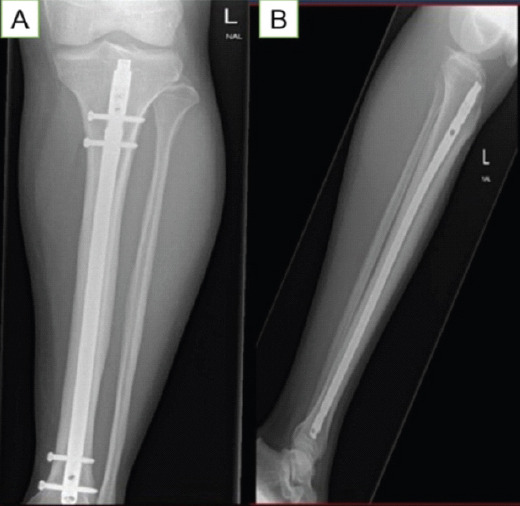

Case report: Here, we discuss a rare clinical case of a sportsman who presented in our hospital. A 26-year-old professional football player presented to us in July 2024 with bilateral leg pain which worsened on playing football. The plain radiograph showed that the middle part of the left side tibial shaft anteriorly had higher density, while the right side was unremarkable; which was further investigated with computed tomography scan on left side on presentation and magnetic resonance imaging on right side on 3 months follow up.

Conclusion: A thorough review of the patient's history is essential when evaluating persistent leg pain associated with repetitive activities. Our report emphasis importance of early recognition and surgical intervention in seeking rapid return to play and be active especially in athletes.